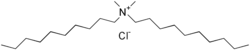

Didecyldimethylammonium chloride

| Preferred IUPAC name

N-Decyl-N,N-dimethyldecan-1-aminium chloride | |

| C22H48ClN | |

| Molar mass | 362.08 g/mol |

Didecyldimethylammonium chloride (DDAC) is a quaternary ammonium compound used as an antiseptic/disinfectant. It causes the disruption of intermolecular interactions and the dissociation of lipid bilayers. The bacteriostatic (prevent growth) or bactericidal (kill microorganism) activity of DDAC depends on its concentration and the growth phase of the microbial population.[4] It is a broad spectrum biocidal against bacteria and fungi and can be used as disinfectant cleaner for linen, recommended for use in hospitals, hotels and industries. It is also used in gynaecology, surgery, ophthalmology, pediatrics, OT, and for the sterilization of surgical instruments, endoscopes and surface disinfection.